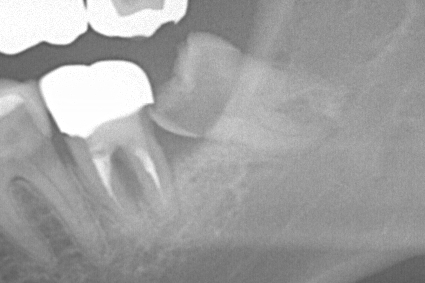

【親知らずのレントゲン写真】

この2例は別々の患者様です。

処置時間として麻酔終了後、15分ほどで終了しております(^^)/